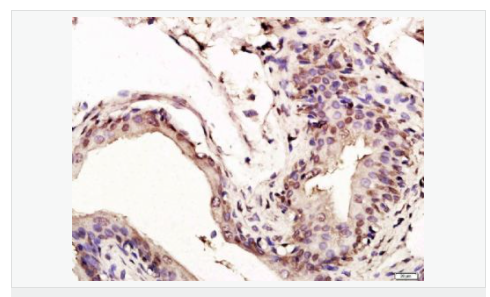

| 产品应用 | WB=1:1000-2000 ELISA=1:1000-5000 IHC-P=1:100-500 IHC-F=1:100-500 Flow-Cyt=1ug/Test ICC=1:100-500 IF=1:100-500 (石蜡切片需做抗原修复) not yet tested in other applications. optimal dilutions/concentrations should be determined by the end user. |

| 细胞定位 | 细胞核 细胞浆 |